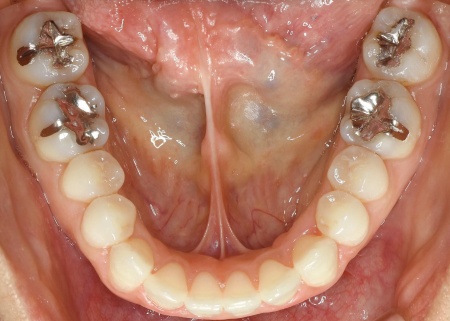

加えて全体的に歯が重なり合ってデコボコに生えており、歯磨きがしにくく、審美性にも悪影響がでています。

さらに舌で前歯を押す癖もあり、これは開咬の原因だけでなく、矯正治療後に歯並びが戻る原因にもなります。

開咬の主な原因は、奥歯の噛み合わせの強さと舌の癖にあると考えられます。

最後に、歯並びが整い前歯で噛めるようになったこと、舌の癖が改善されたことを確認し、治療を終了しています。